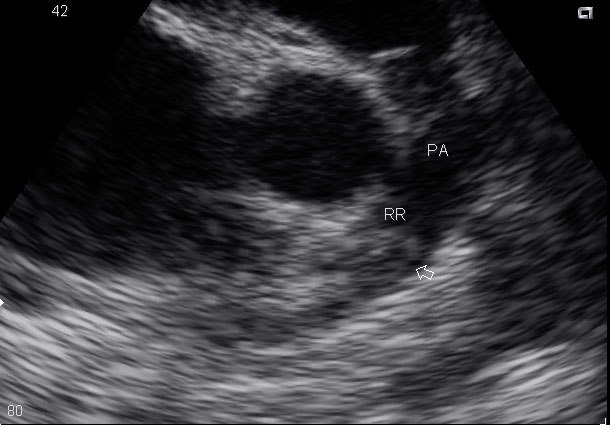

ПОСЛЕ ОПЕРАЦИИ ПО ПОВОДУ ГРЫЖИ МЕЖПОЗВОНОЧНЫХ ДИСКОВ ПОЯСНИЧНОГО ОТДЕЛА МОЛОДАЯ ЖЕНЩИНА ПОПАДАЕТ В РАО С СИМПТОМАМИ ТРОМБОЭМБОЛИИ. НА ЭХО ПОЛУЧИЛАСЬ ВОТ ТАКАЯ КАРТИНКА. ВАШЕ МНЕНИЕ, КОЛЛЕГИ, ВОЗМОЖНАЯ ТАКТИКА.

ТЛТ успешно проведена, размеры камер сердца в пределах нормы, легочной гипертензии нет, тромб не визуализируется. Правда нет гарантий, что все участки тромба до конца растворились, в правой ветви долгое время сохранялся измененный кровоток.